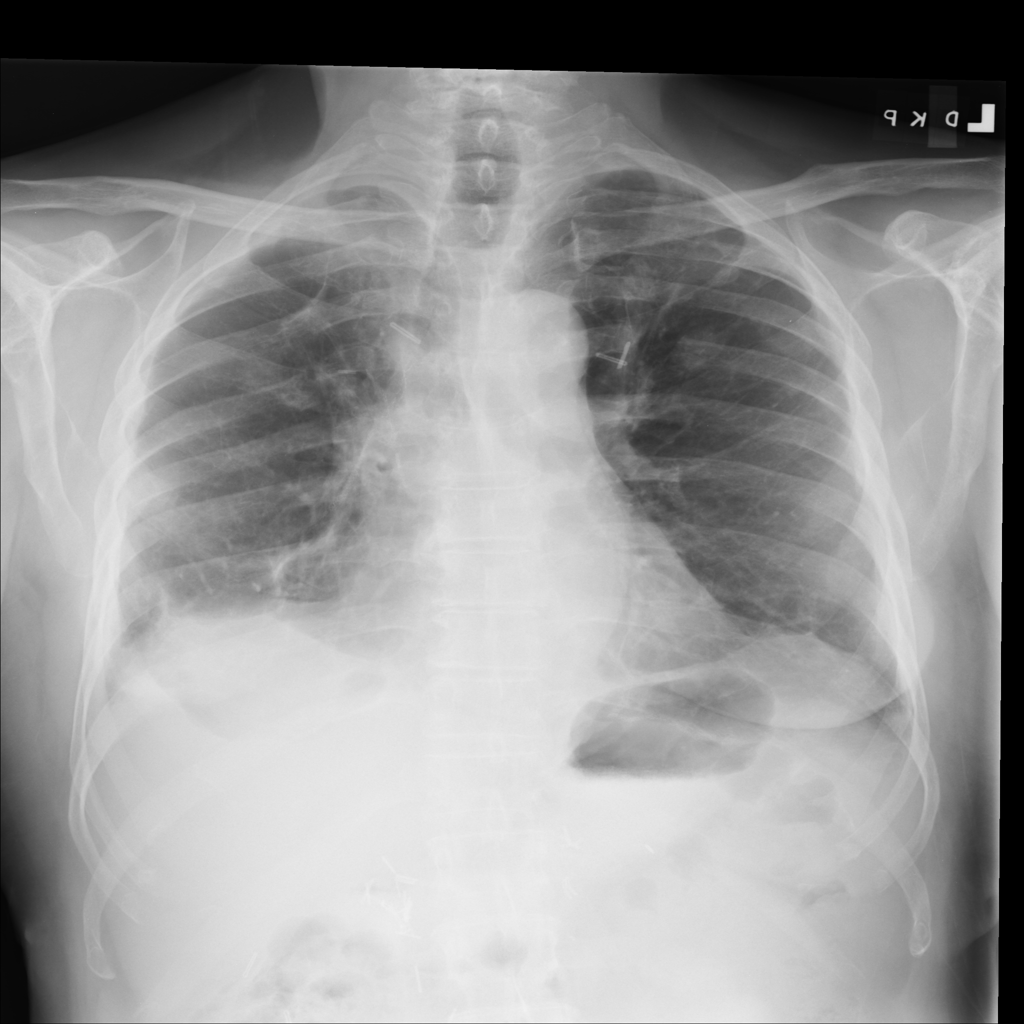

PAT-40F9 · IMG-004Effusion

PAT-40F9 · IMG-004

PA